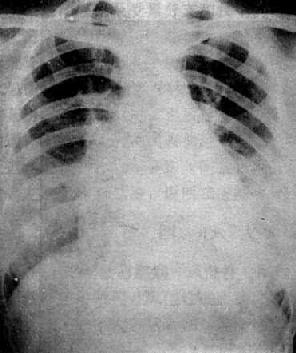

图3-2-17 慢性肺原性心脏病

心呈二尖瓣型,右心室增大,肺动脉突出,但无左心耳增大。肺动脉扩张,尤以右下肺动脉为明显,有肺门截断现象,说明有肺动脉高压。肺纹理增强,肺透明度增加,膈平而低,说明有慢性支气管炎和肺气肿。